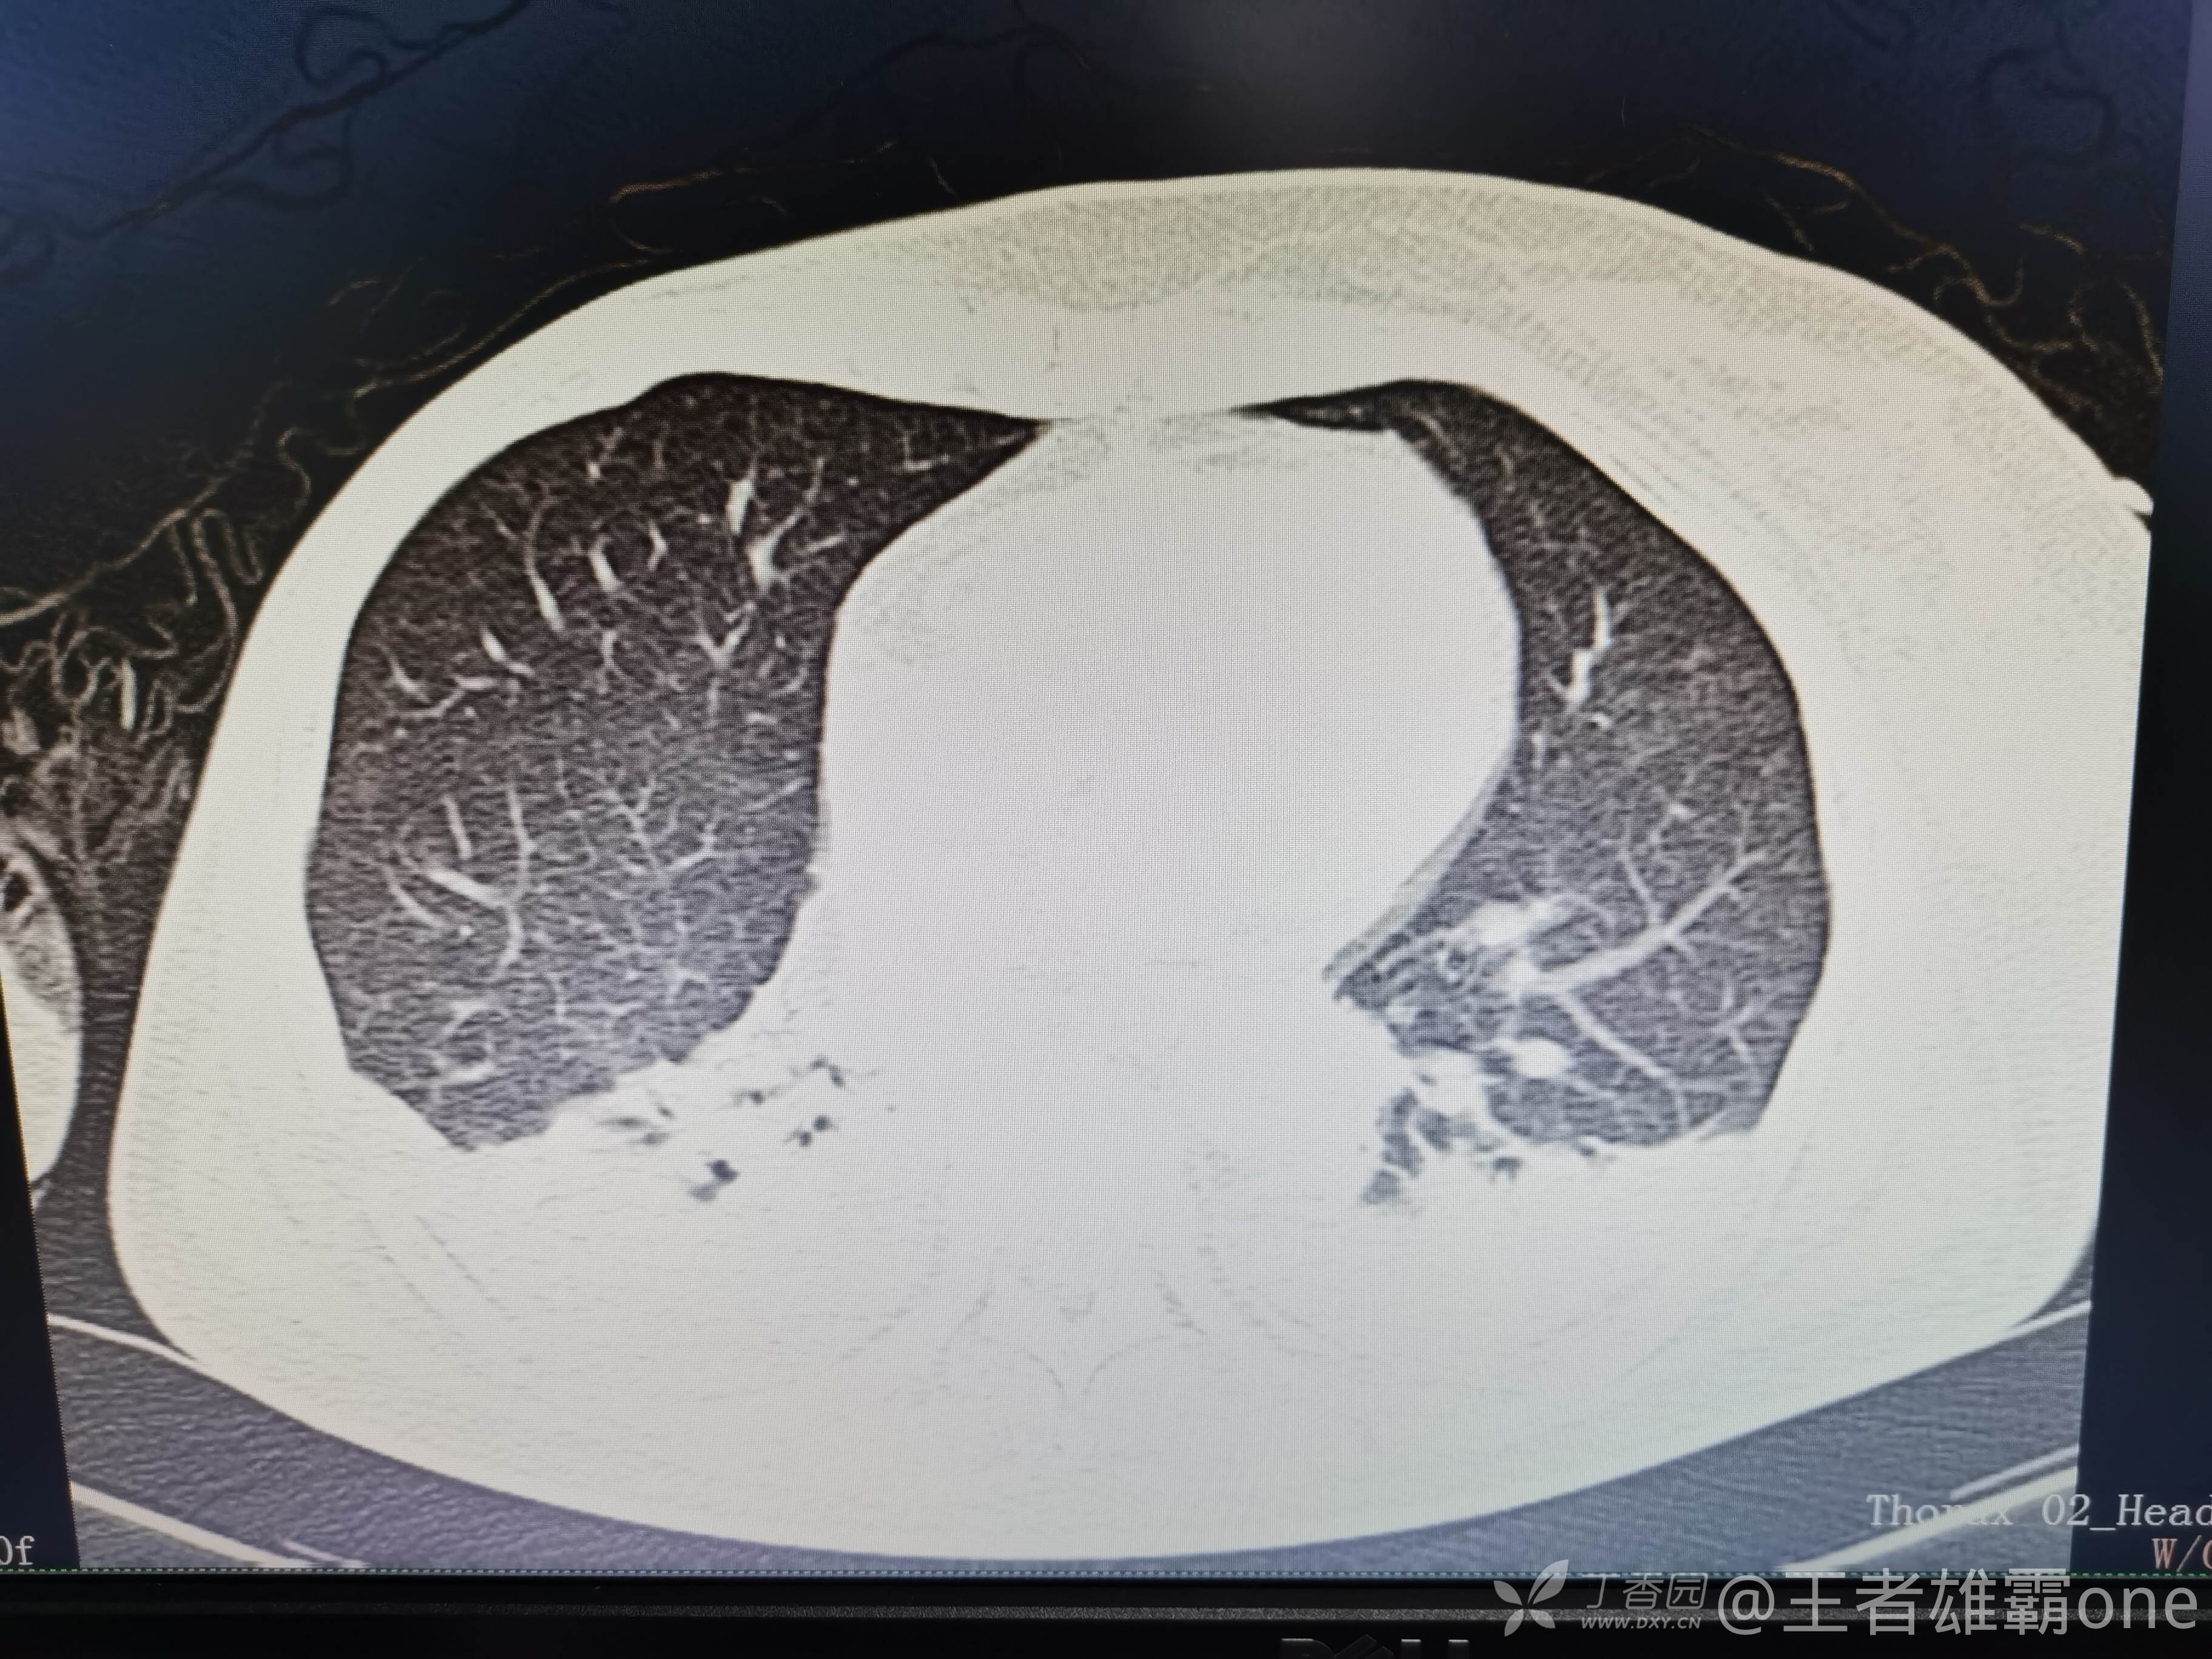

西门开心 推荐63岁女性,因车祸致短暂神志不清、多处疼痛4h入院。简单病史:伤后送至医院急诊就诊。完善头胸腹CT等检查,完善新冠核酸、血常规等化验。血常规提示血红蛋白62g/L。头颅CT提示未见明显外伤性改变。胸腹部CT视频见下:

5.肺挫伤

6.双侧多发肋骨骨折

12.双侧胸腔少量积液

早上复查血常规:血红蛋白100g/L,白细胞11.1×109/L,血小板29×109/L。凝血功能:APTT37.9s,纤维蛋白原3.01g/L,凝血酶时间18.6s,D二聚体21530ug/L。生化:白蛋白36.2g/L,胆红素指标正常,谷丙56U/L,总胆红素38mmol/L,直接胆红素12.1mmol/L,谷草57U/L,肌酐91.1ummol/L,尿素13.97mmol/L,超敏C反应蛋白142.1mg/L。降钙素原17.70ng/ml。脑钠肽前体2164pg/ml。复查胸部CT:

那么问题来了,出现呼吸衰竭气管插管的病因是?请大家讨论分析!